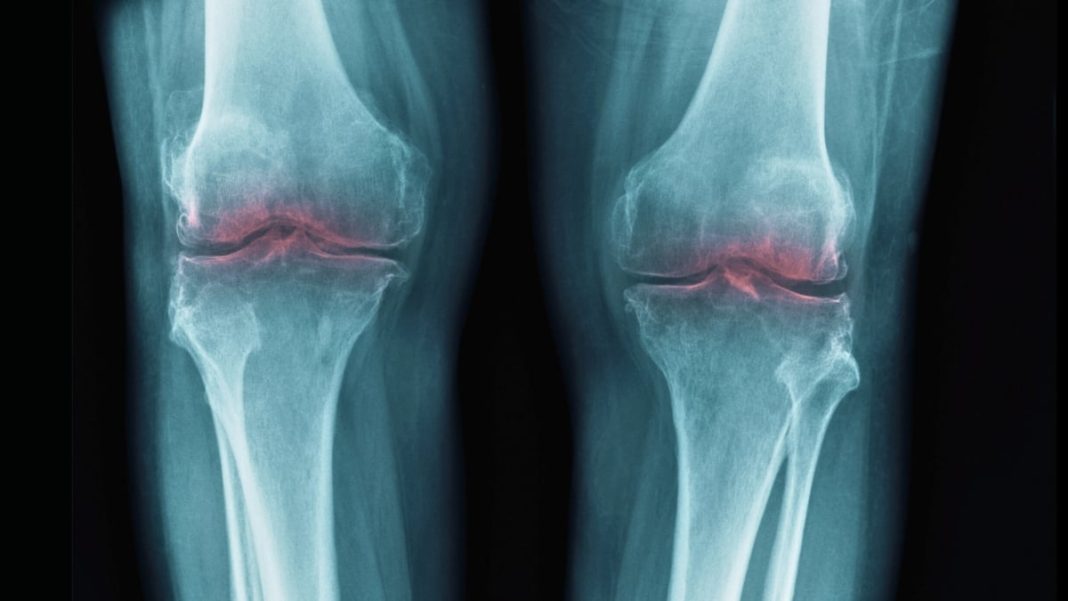

Osteoarthritis isn’t merely a condition of aging; it’s a degenerative joint disease where the protective cartilage that cushions the ends of your bones gradually wears down. This leads to bone-on-bone friction, causing pain, swelling, and reduced mobility. Imagine the tires on your car slowly eroding until the metal rims scrape the road – that’s a crude but effective analogy for the daily agony OA sufferers endure. Current interventions, while valuable, often feel like temporary fixes. Painkillers, anti-inflammatory drugs, physical therapy, and even corticosteroid injections offer symptomatic relief. Joint replacement surgery, while transformative for many, is an invasive procedure with a finite lifespan, typically reserved for the most severe cases. The fundamental problem, the degenerating cartilage, has remained largely beyond our direct ability to repair or regenerate effectively. Until now.